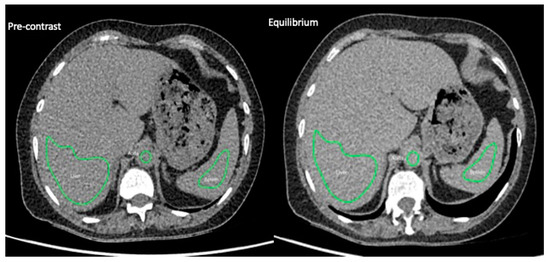

2.3. EQ-CT

2.4. CTTA